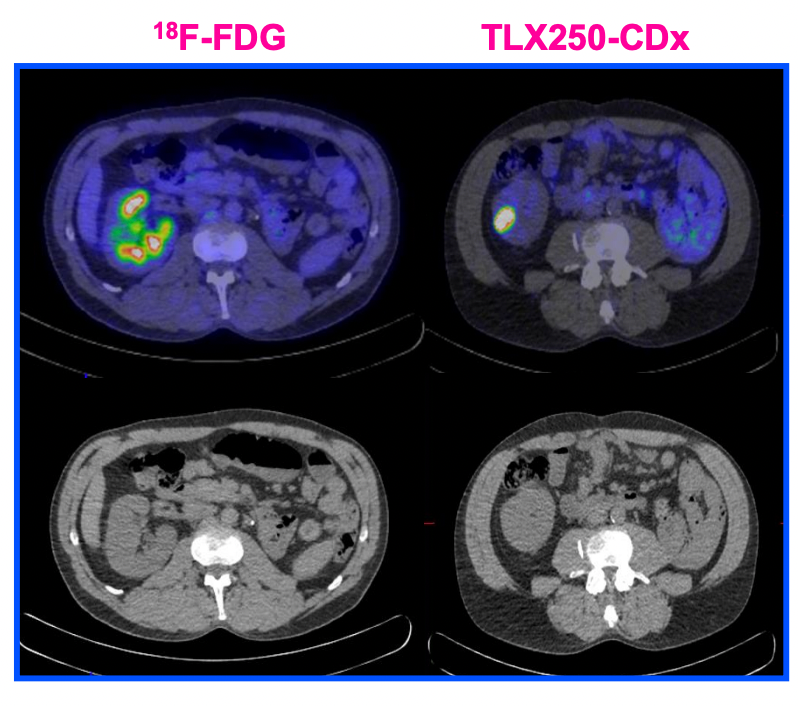

Dive into the stunning world of abstract Renal Cancer Pet/ct with vast arrays of imaginative images. highlighting the innovative use of photography, images, and pictures. ideal for modern art and design. Browse our premium Renal Cancer Pet/ct gallery featuring professionally curated photographs. Suitable for various applications including web design, social media, personal projects, and digital content creation All Renal Cancer Pet/ct images are available in high resolution with professional-grade quality, optimized for both digital and print applications, and include comprehensive metadata for easy organization and usage. Our Renal Cancer Pet/ct gallery offers diverse visual resources to bring your ideas to life. Time-saving browsing features help users locate ideal Renal Cancer Pet/ct images quickly. Reliable customer support ensures smooth experience throughout the Renal Cancer Pet/ct selection process. Cost-effective licensing makes professional Renal Cancer Pet/ct photography accessible to all budgets. Professional licensing options accommodate both commercial and educational usage requirements. Diverse style options within the Renal Cancer Pet/ct collection suit various aesthetic preferences. The Renal Cancer Pet/ct collection represents years of careful curation and professional standards. Each image in our Renal Cancer Pet/ct gallery undergoes rigorous quality assessment before inclusion. Multiple resolution options ensure optimal performance across different platforms and applications.